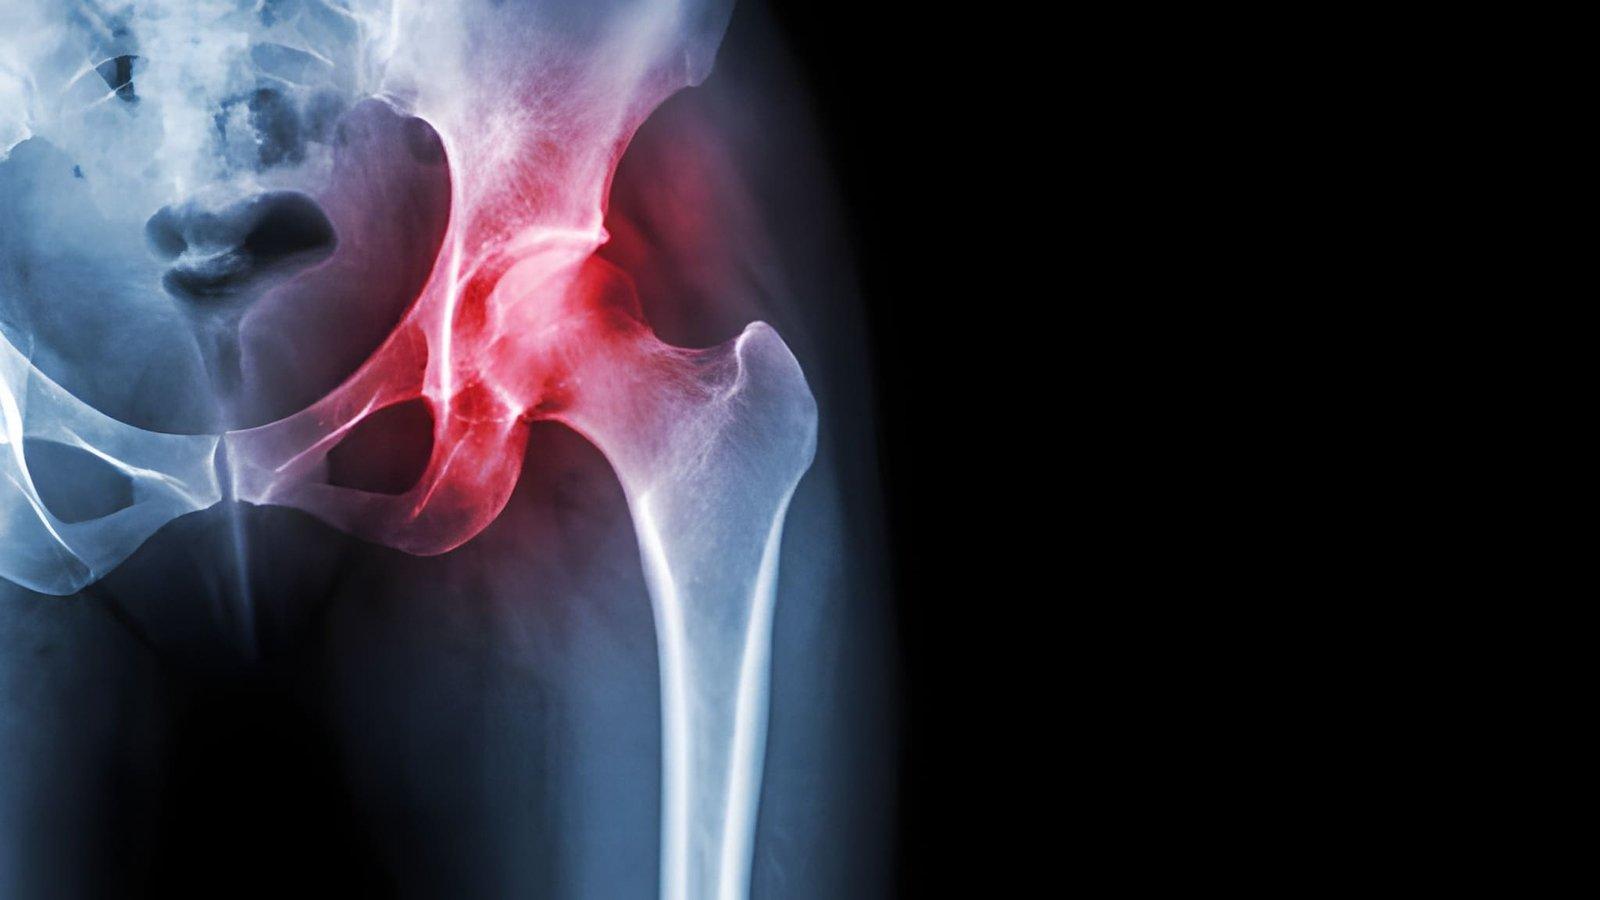

Avascular necrosis (AVN), also known as osteonecrosis, is a progressive condition caused by reduced blood supply to bone tissue, ultimately leading to bone damage and joint dysfunction. It most commonly affects the hip, knee, shoulder, and ankle, often resulting in chronic pain and restricted movement. While individuals of all ages can develop AVN, it is most frequently diagnosed in adults between 30 and 60 years old. Growing clinical attention and rising patient numbers have placed the Avascular Necrosis Market at the forefront of healthcare discussions, as stakeholders work toward improved treatment outcomes.

The expansion of this market is largely driven by an increase in risk factors such as prolonged steroid use, excessive alcohol intake, trauma, and chronic diseases. Disorders like sickle cell anemia, lupus, and HIV are contributing significantly to the rising incidence of AVN. At the same time, advancements in imaging technologies, particularly MRI, are enabling earlier and more accurate diagnosis. Findings from Avascular Necrosis Market Research emphasize the growing need for innovative treatment solutions to address the increasing disease burden.

Treatment for AVN has evolved significantly, offering a range of options depending on disease severity. Early-stage management typically involves medications such as bisphosphonates and vasodilators to delay progression. Surgical techniques, including core decompression and bone grafting, aim to preserve joint function, while advanced cases often require joint replacement procedures. Emerging therapies like stem cell treatments and platelet-rich plasma injections are gaining attention for their regenerative potential. According to recent Avascular Necrosis Market Insight, there is a clear shift toward less invasive and joint-preserving interventions.